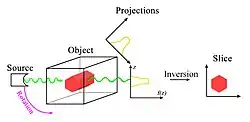

In mathematics, the Radon transform is the integral transform which takes a function f defined on the plane to a function Rf defined on the (two-dimensional) space of lines in the plane, whose value at a particular line is equal to the line integral of the function over that line. The transform was introduced in 1917 by Johann Radon,[1] who also provided a formula for the inverse transform. Radon further included formulas for the transform in three dimensions, in which the integral is taken over planes (integrating over lines is known as the X-ray transform). It was later generalized to higher-dimensional Euclidean spaces and more broadly in the context of integral geometry. The complex analogue of the Radon transform is known as the Penrose transform. The Radon transform is widely applicable to tomography, the creation of an image from the projection data associated with cross-sectional scans of an object.

If a function represents an unknown density, then the Radon transform represents the projection data obtained as the output of a tomographic scan. The inverse of the Radon transform can be used to reconstruct the original density from the projection data, and thus it forms the mathematical underpinning for tomographic reconstruction, also known as iterative reconstruction.